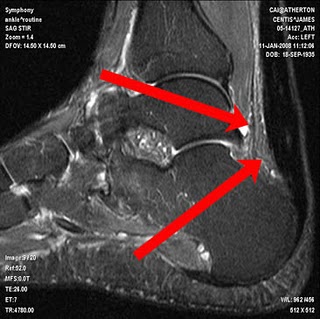

Now, though, the first rigorous study asking whether the platelet injections actually work finds they are no more effective than saltwater. The study, reported in the Jan. 13 issue of The Journal of the American Medical Association, involved people with injured Achilles’ tendons, fibrous tissue that connects the calf to the heel bone.